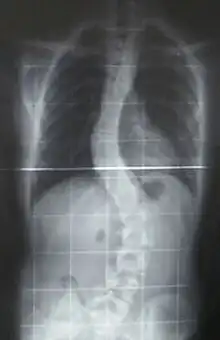

Cobb angle is a common measure to classify scoliosis. The greater the angle, the more serious is the disease but the smaller is the number of patients. One to three out of every hundred people have idiopathic scoliosis curves greater than 10° with an equal proportion of boys and girls. One to three out of every thousand people have idiopathic scoliosis curves greater than 30° with a ratio of eight girls for every one boy.[12]

Scoliosis is also classified according to the region(s) they affect. The vertebral column can be deformed at the thoracic level, at the lumbar level or at both. In the lumbar region, scoliosis induces perturbations to standing balance. The thoracic region is the location that most impacts movement strategies.[13] Scoliosis impedes on the movement of the ribs, places the respiratory muscles at a mechanical disadvantage and displaces the various organs of the thoracic cavity.[14]